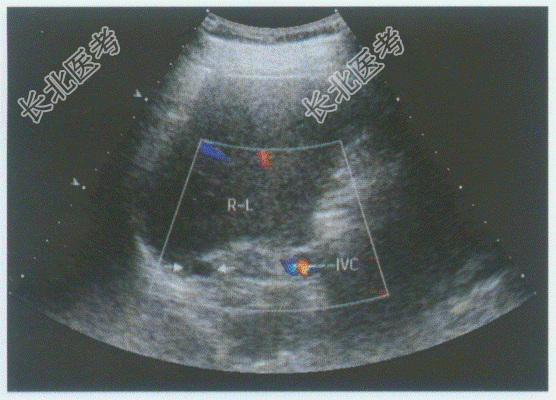

- 单项选择题临床资料:男性患者, 67岁,自述患高血压、糖尿病20年余。长期服用降压药, 血压控制好。

超声综合描述:肝右叶后方与下腔静脉间可见0.8cm×1.0cm类圆形低回声区(箭头所示), 边界清晰,CDFI: 内未见动静脉血流信号。见彩图。

超声提示: A、右膈下占位

B、下腔静脉内癌栓

C、右肾上腺结节

D、肝右叶结节

E、肝硬化